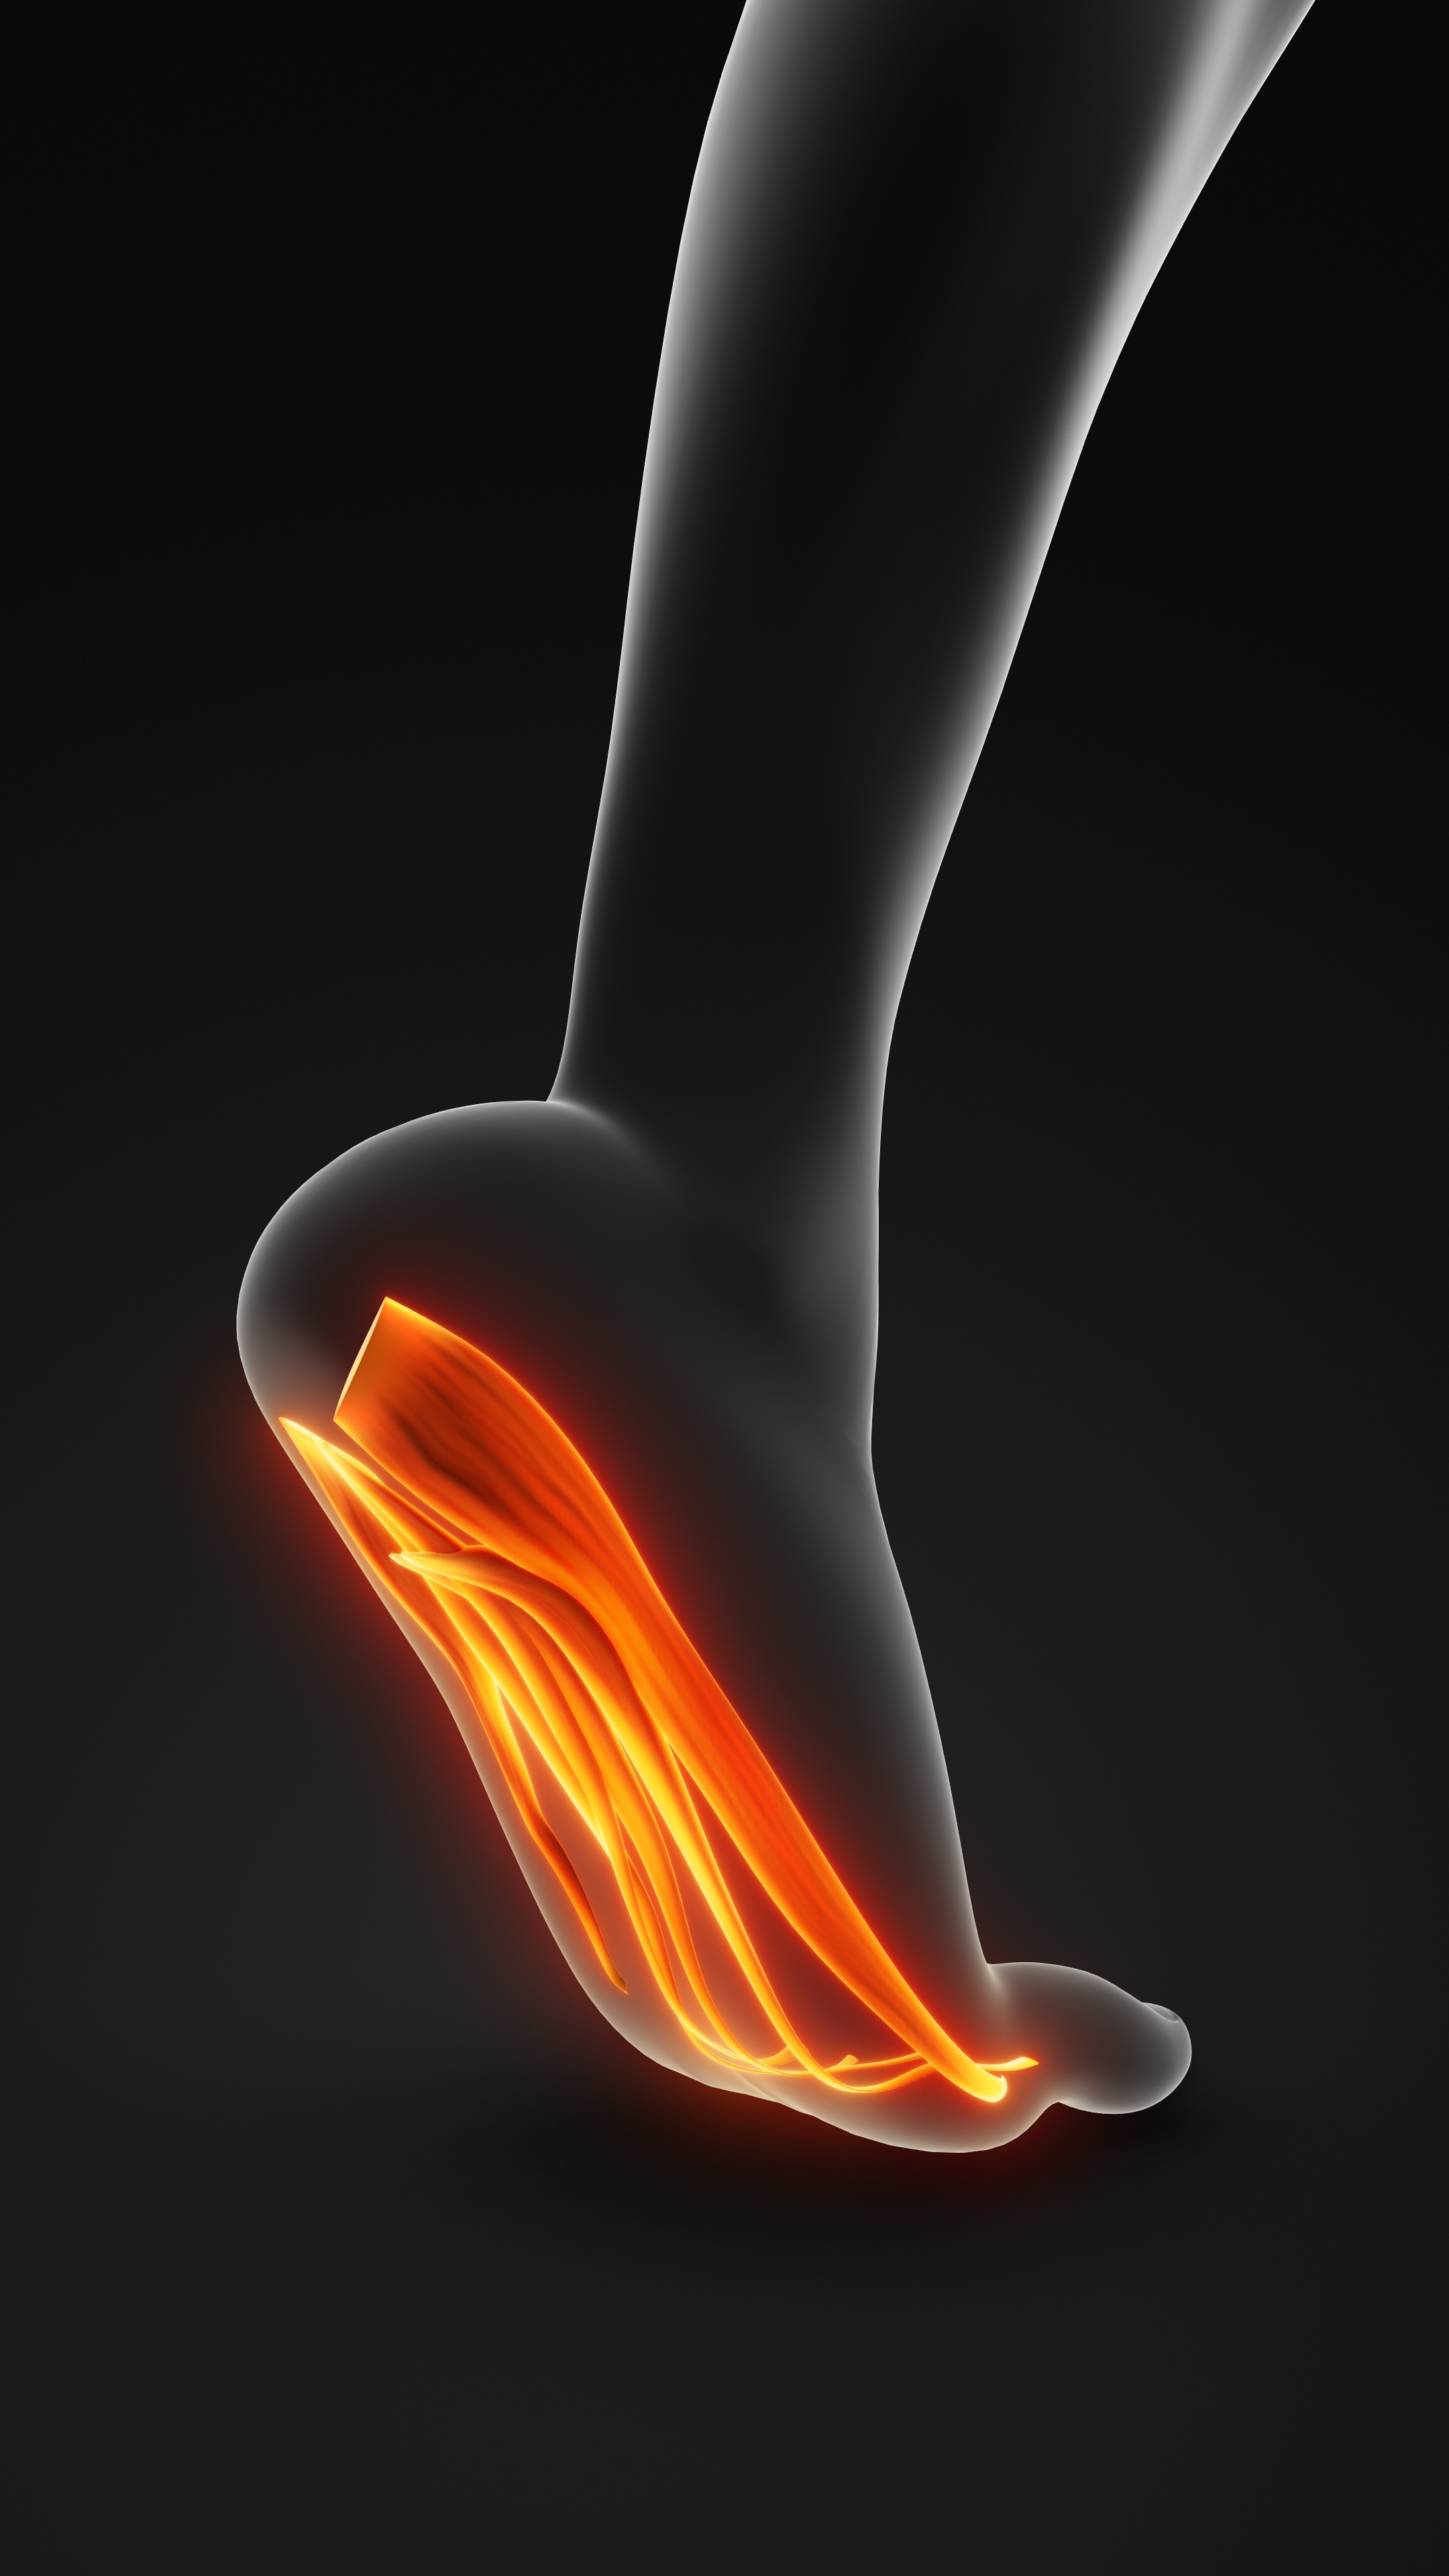

Πρόκειται για μία πολύ επώδυνη φλεγμονή στην πελματιαία απονεύρωση, η οποία είναι τμήμα της πελματιαίας περιτονίας που συνδέει, ως πυκνός ινώδης ιστός, την πτέρνα με τις κεφαλές των πέντε μεταταρσίων του άκρου ποδός. Η πελματιαία απονεύρωση βρίσκεται μονιμά σε τάση, διατηρώντας με τον τρόπο αυτό την ποδική καμάρα. Η πάθηση ανήκει στα σύνδρομα υπέρχρησης και αφορά σε φλεγμονή στο σημείο έκφυσης της απονεύρωσης από την πτέρνα. Είναι μια από τις συχνότερες αιτίες πόνου στην περιοχή της πτέρνας.